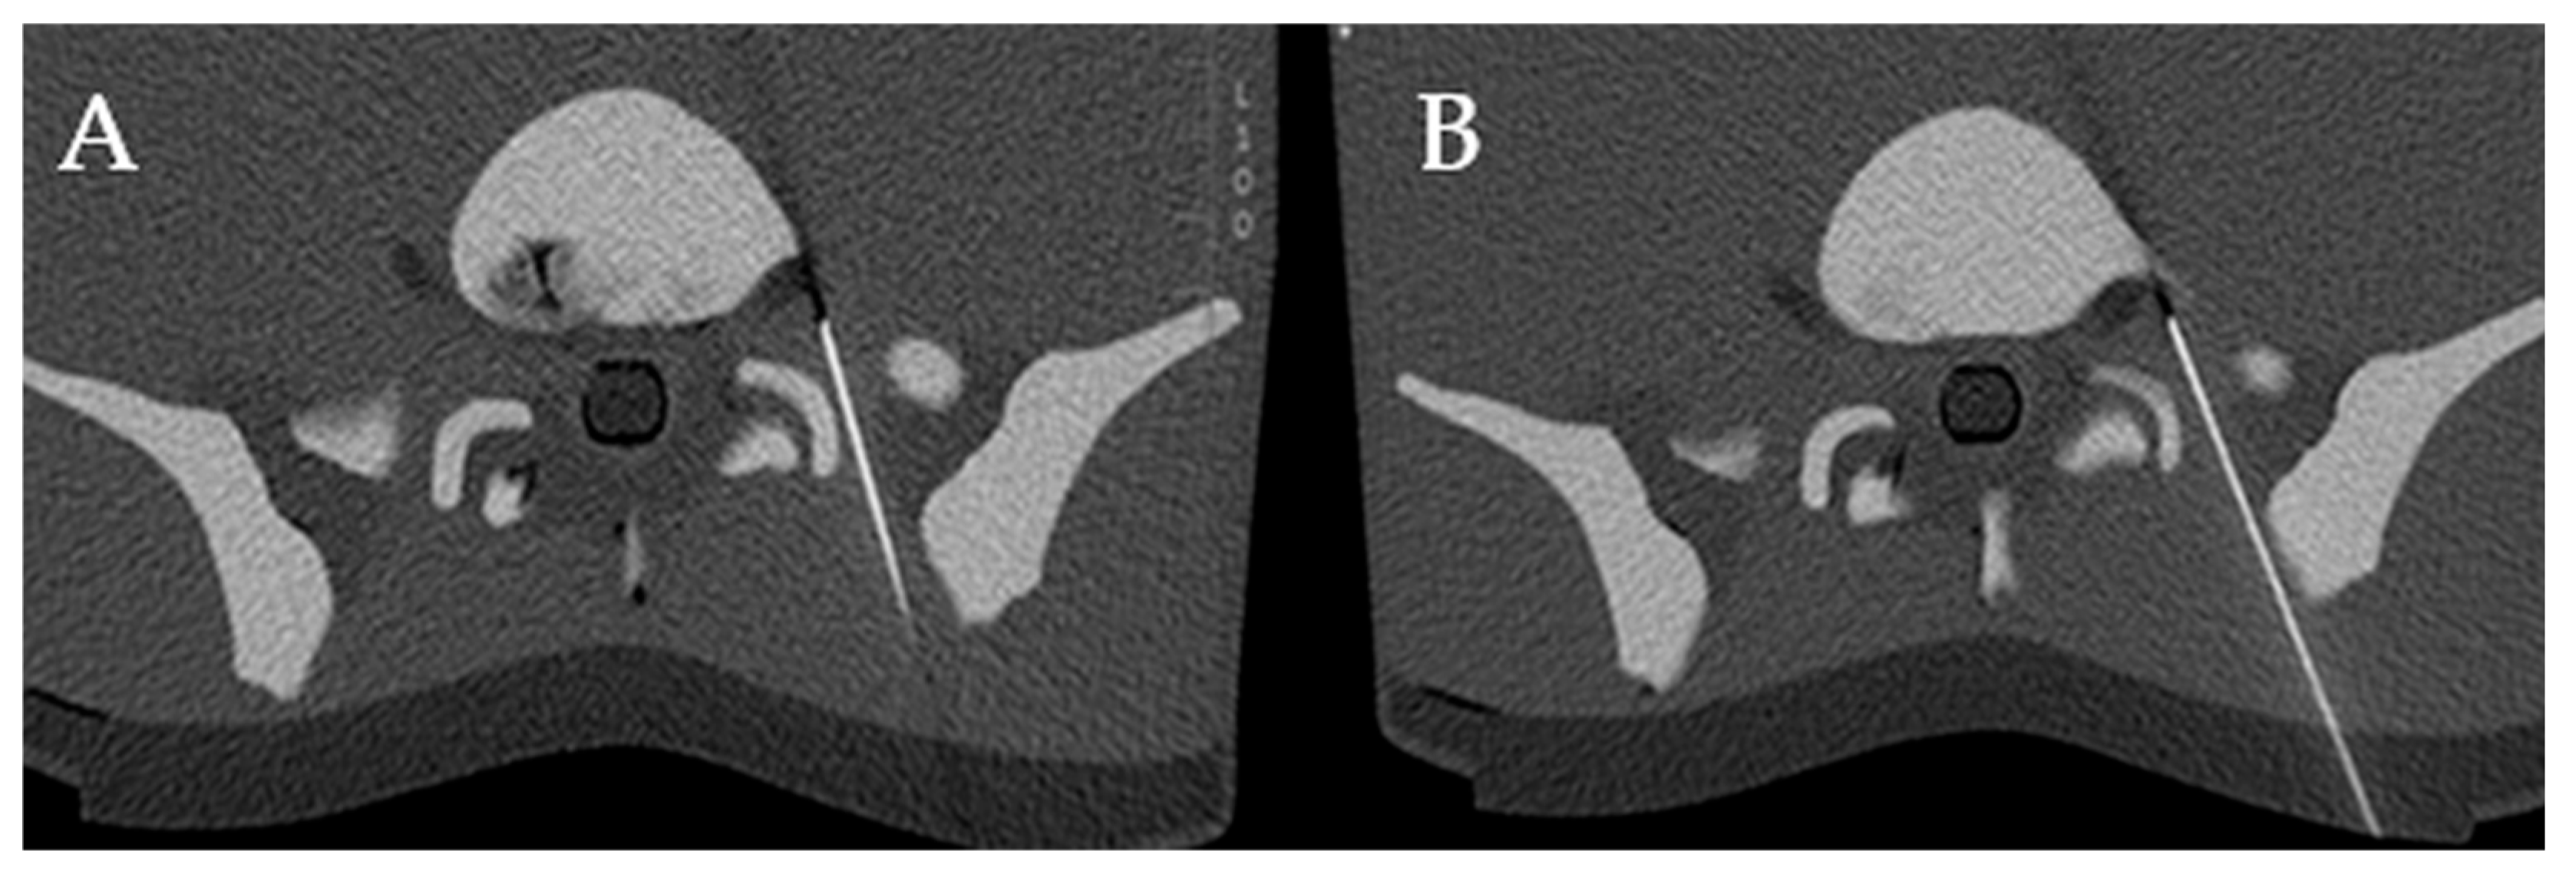

2.1. Study Design

2.4. 3D Laser MDCT Guidance System

2.5. Conventional Needle Guidance

4.3. Distance from Needle Tip to the Nerve Root